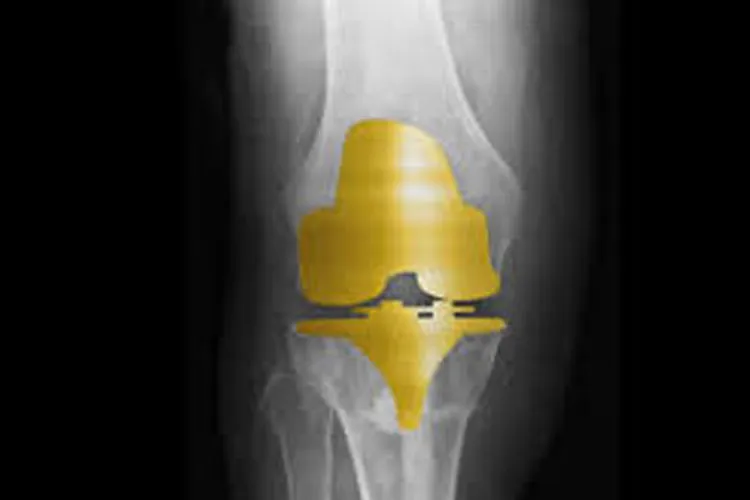

देश में तेजी से बढ़ रहा 'गोल्डन नी इंप्लांट' का चलन, सिर्फ 1 घंटे में सर्जरी

हेल्थ डेस्क: देश में घुटने बदलने की सर्जरी में 'गोल्डन नी इंप्लांट' का उपयोग तेजी से बढ़ने लगा है। पिछले करीब ढाई महीने के भीतर अकेले इंद्रप्रस्थ अपोलो अस्पताल में ही 25 मरीजों की 'गोल्डन नी इम्प्लांट' सर्जरी हुई है। अस्पताल के वरिष्ठ आर्थोपेडिक एवं ज्वाइंट रिप्लेसमेंट सर्जन डॉ. राजू वैश्य ने कहा, "इस साल 26 मई को अस्पताल में पहली गोल्डन नी इंप्लांट सर्जरी की गई थी और तब से लेकर अब तक करीब 25 गोल्डन नी इंप्लांट सर्जरी हो चुकी है। इस सर्जरी में एक घंटे का समय लगता है।"

डॉ. राजू वैश्य ने बताया कि गोल्डन नी इंप्लांट का इस्तेमाल होने के कारण मरीजों को दोबारा घुटने की सर्जरी कराने की जरूरत खत्म हो गई है। धातु के परम्परागत इंप्लांट में एलर्जी के कारण इंप्लांट के खराब होने का खतरा होता था जिससे कई मरीजों को दोबारा घुटना बदलवाना पड़ता था लेकिन गोल्डन नी इंप्लांट में एलर्जी का खतरा नहीं होता और साथ ही यह इंप्लांट 30 से 34 साल तक चलता है जिसके कारण यह कम उम्र के मरीजों के लिए भी उपयोगी है।

डॉ. राजू वैश्य ने बताया कि परंपरागत इंप्लांट की तुलना में 'गोल्डन नी इंप्लांट' बहुत सस्ता है और जिन्हें घुटना बदलवाने की सर्जरी की जरूरत है, वे आसानी से इसके खर्च को वहन कर सकते हैं। इस इंप्लांट के कारण मरीज घुटने को पूरी तरह से मोड़ सकते हैं, पालथी मार कर बैठ सकते हैं, झुक सकते हैं और आराम से सीढ़ियां भी चढ़ सकते हैं।